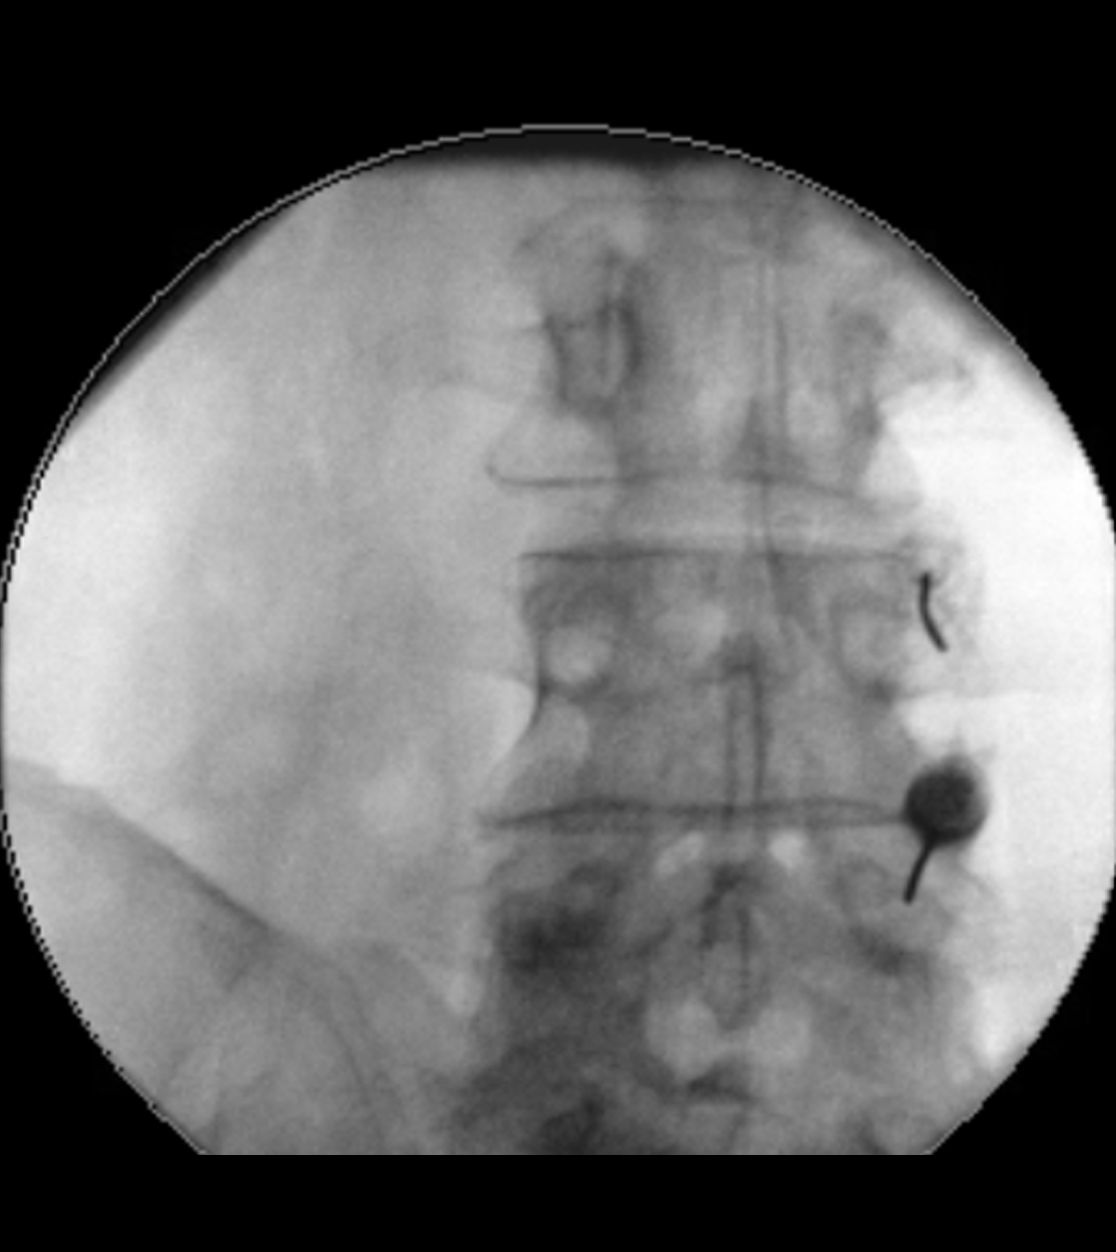

Im Nervenwasserraum (Liquor) einliegender Schlauch zur intrathekalen Therapie (Pfeil)

Sollte bei einer Trigeminusneuralgie eine mikrovaskuläre Dekompression nicht infrage kommen, so kann als minimalinvasives Verfahren eine „Verödung“ des Ganglion Gasseri zu einer Schmerzlinderung führen. Hierbei wird unter Röntgenkontrolle eine dünne Nadelelektrode in das Ganglion Gasseri geschoben und mit gezielten Wärmestrahlen eine selektive Vernarbung der Nervenfasern vorgenommen, die für die Schmerzübertragung verantwortlich sind. In einigen Fällen ist im Verlauf bei einer erneuten Zunahme der Beschwerden eine Wiederholung der Prozedur notwendig.